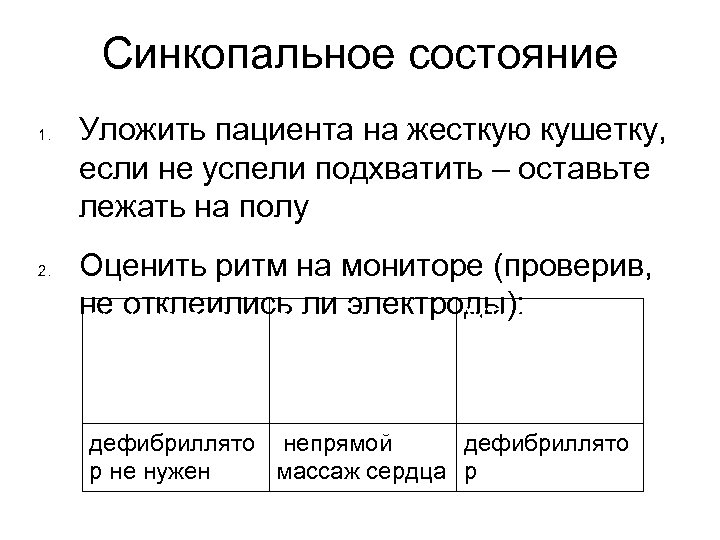

Синкопальное состояние 1. 2. Уложить пациента на жесткую кушетку, если не успели подхватить – оставьте лежать на полу Оценить ритм на мониторе (проверив, не отклеились ли электроды): син/предсердн редкие ЖТ/ ФЖ ый ритм желудочковые сокращения/ асистолия дефибриллято непрямой дефибриллято р не нужен массаж сердца р

Синкопальное состояние 1. 2. Уложить пациента на жесткую кушетку, если не успели подхватить – оставьте лежать на полу Оценить ритм на мониторе (проверив, не отклеились ли электроды): син/предсердн редкие ЖТ/ ФЖ ый ритм желудочковые сокращения/ асистолия дефибриллято непрямой дефибриллято р не нужен массаж сердца р